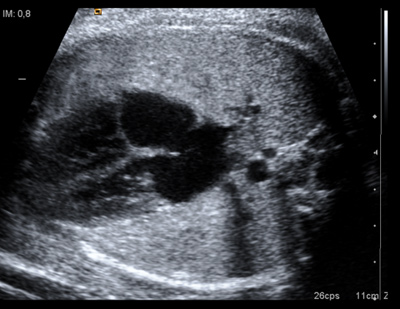

Se trata de un software, quantusFLM, disponible a través de una aplicación web que evalúa imágenes ecográficas en 2D de la zona pulmonar fetal. Es capaz de determinar si el bebé está listo para respirar o no. El sistema presenta una fiabilidad simular a los métodos disponibles hasta la fecha, basados en una prueba invasiva, la amniocentesis.

Se trata de un "software" que analiza una ecografía. Necesitamos que el ginecólogo realice una ecografía de los pulmones del feto: en unos diez minutos, nuestro programa examina la imagen ecográfica pulmonar y es capaz de dar un diagnóstico fiable sobre la madurez pulmonar. ¿Cómo? El doctor accede a nuestro programa a partir de una aplicación web y "sube" la ecografía para que el sistema la analice.

La base es el procesado de la imagen. Nuestro software ha aprendido a reconocer parámetros y características dentro de la imagen que se correlacionan con el estado madurativo del pulmón fetal. Se trata de una aplicación web, en la que subiendo una imagen ecográfica de los pulmones del feto se puede determinar de forma fiable, no invasiva y rápida, la madurez pulmonar fetal. El doctor no tiene que instalarse ningún programa y no es necesario que tenga ningún conocimiento sobre el procesado de imagen, ya que el proceso es automático para el usuario final.

Necesitamos imágenes ecográficas en 2D normales. Lo que pedimos al ginecólogo es una imagen en el plano de las cuatro cámaras del corazón fetal, que muestra muy bien los pulmones. Esta imagen la toma el ecografista perfectamente, está muy habituado hacerla porque es necesaria para evaluar el corazón del bebé.